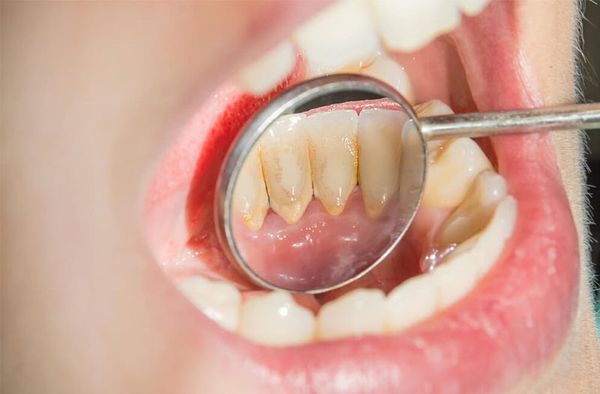

Cao răng khiến cho hàm răng mất thẩm mỹ Cao răng khiến cho hàm răng mất thẩm mỹ

Cao răng, hay còn gọi là vôi răng, là mảng bám đã bị vôi hóa bởi các khoáng chất trong nước bọt, hình thành dưới và trên đường viền nướu.

Vi khuẩn luôn tồn tại trong miệng, ngay cả khi đã vệ sinh răng miệng. Chúng kết hợp với protein và thức ăn thừa, tạo thành mảng bám răng. Mảng bám này phủ lên răng và sau một thời gian sẽ cứng lại, trở thành cao răng, không thể loại bỏ bằng cách chải răng thông thường.

Cao răng chứa nhiều vi khuẩn, làm hỏng men răng và khiến nướu thô ráp, xốp, có thể tụt khỏi răng. Cao răng chỉ có thể được loại bỏ bằng các biện pháp vệ sinh răng miệng chuyên nghiệp. Nếu không được làm sạch, cao răng sẽ gây các bệnh về nướu, bao gồm viêm nha chu nguy hiểm.